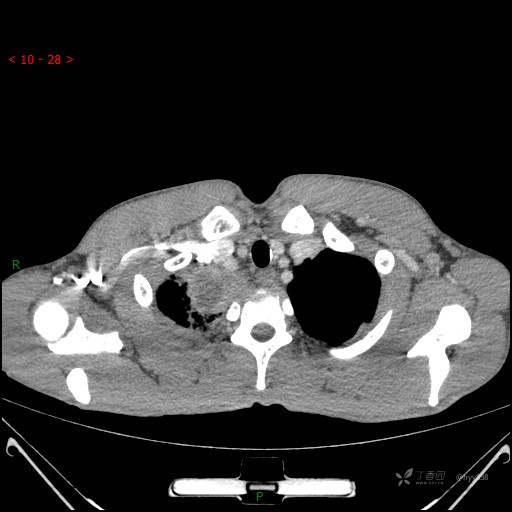

辅助检查:CT

增强动脉期